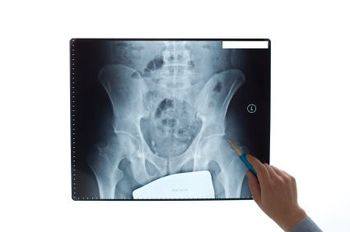

TeleECHO educational programs for healthcare providers have successfully trained physicians and other healthcare providers to fulfill the unmet needs of patients without access to specialty care, particularly osteoporosis care. In this interview with Dr. Michael Lewiecki, he introduces us to Bone Health TeleECHO. He tells us how the program works, why it’s needed and how you can launch one in your state.